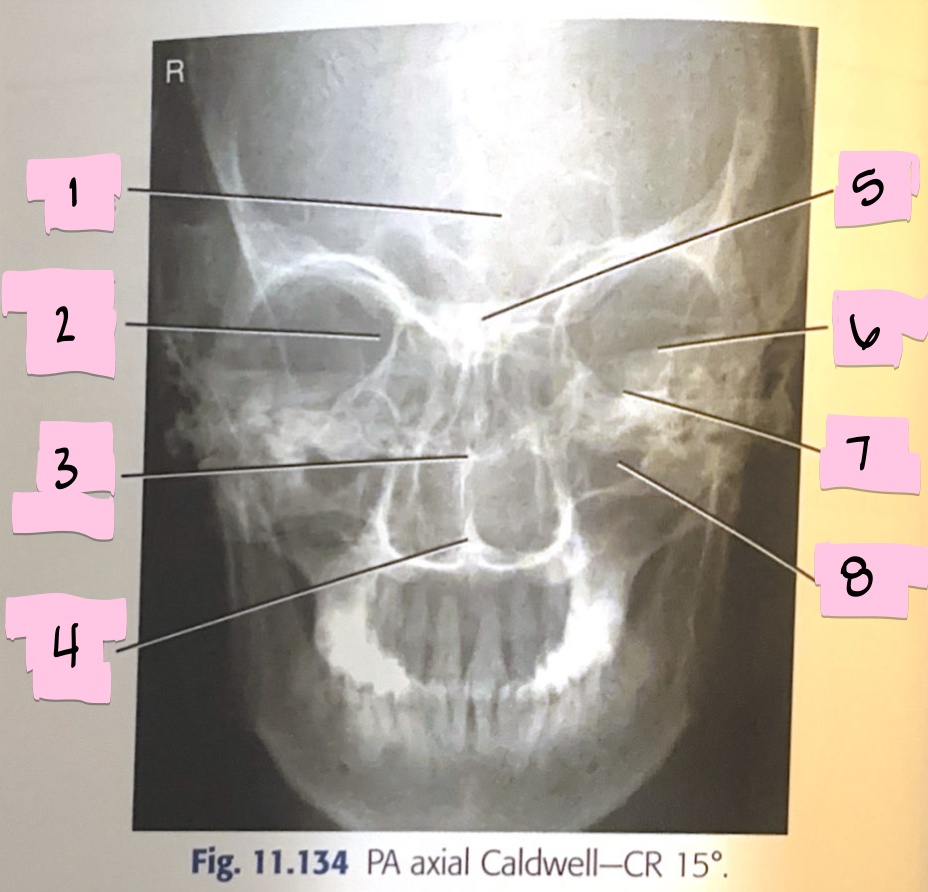

What is 1 pointing to?

Frontal sinus

What is 2 pointing to?

Superior orbital fissure

What is 3 pointing to?

Bony nasal septum

What is 4 pointing to?

Anterior nasal spine

What is 5 pointing to?

Crista galli

What is 6 pointing to?

Petrous ridge

What is 7 pointing to?

Floor of orbit

What is 8 pointing to?

Maxillary sinus